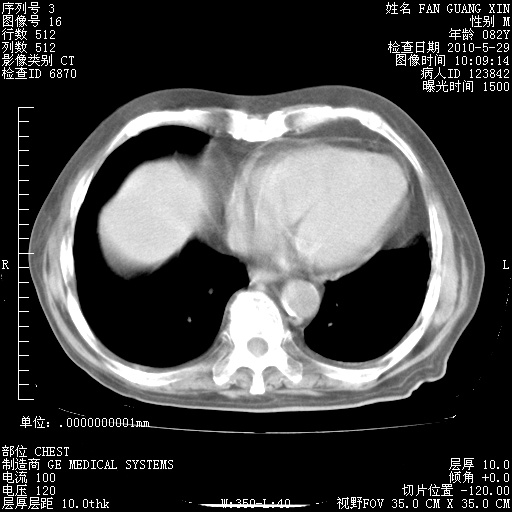

治疗3周后的肺部CT纵隔窗

再治疗10天后的肺部CT

再治疗10天后的肺部CT 纵膈窗

阅读此次胸部CT,肺间质渗出性改变较入院时有吸收。目前从体温、白细胞、中性分叶明显增高,肯定存在细菌感染(发生医院感染哦,若无消化道及泌尿系统等感染的依据,肺部感染可能大)。若你院头孢哌酮舒巴坦钠耐药率较高,同意你的方案,若48小时体温仍高,可考虑使用碳青霉稀类抗菌药物,同时可予超声雾化、注意滴数时加大液体量。白蛋白33.30g/L较低哦,需加强营养等支持治疗。